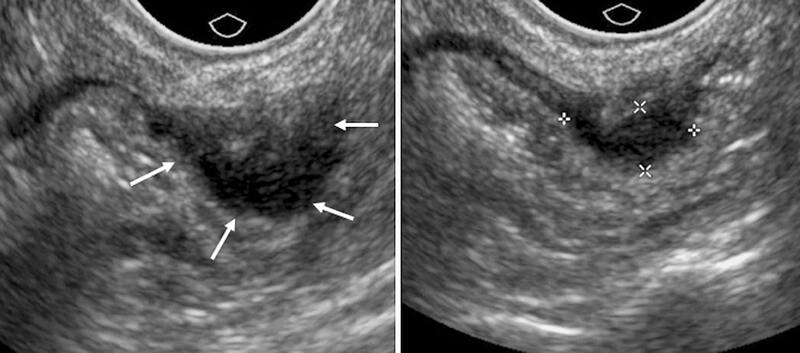

Для определения наличия эндометриоза используются жалобы пациентки, анамнез, а также инструментальные методы исследования. Хотя УЗИ-диагностика помогает оценить состояние репродуктивных органов, она не всегда может точно выявить эндометриоидные очаги. Лапароскопия и магнитно-резонансная томография с контрастом являются более точными методами. Также часто для изучения матки используется гистероскопия, а при наличии признаков спаек в матке и трубах применяется гистеросальпингография. Для выбора подходящей терапии важно сдать анализы на уровень половых гормонов.

Фото: Диагностика наружного эндометриоза